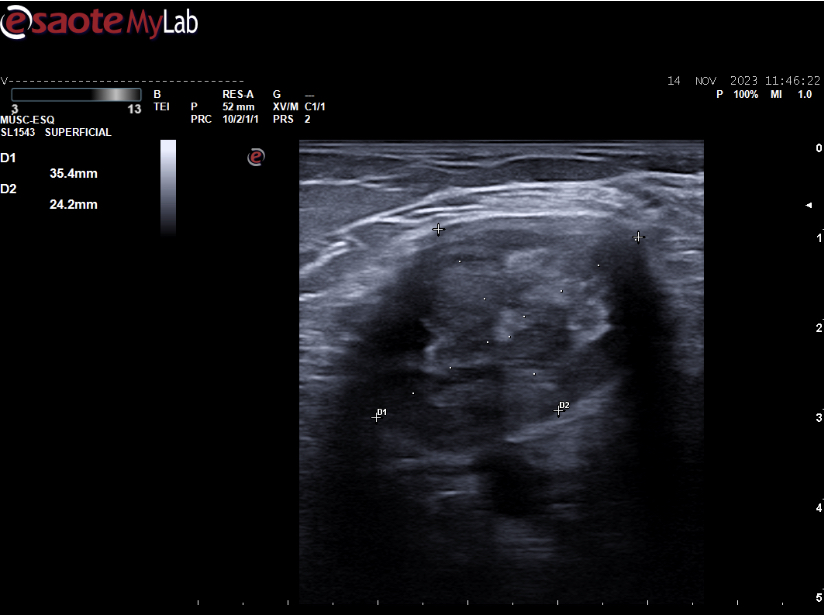

Hallazgos ecográficos

Masa heterogénea de 46*24 mm (zonas hipoecoicas con otras hiperecoicas y zona de microcalcificaciones) con escasa captación Doppler situada superficial al paquete vascular. No se observa lesión quística en la localización teórica del quiste de Baker.

se solicita ecografía reglada a Rayos.